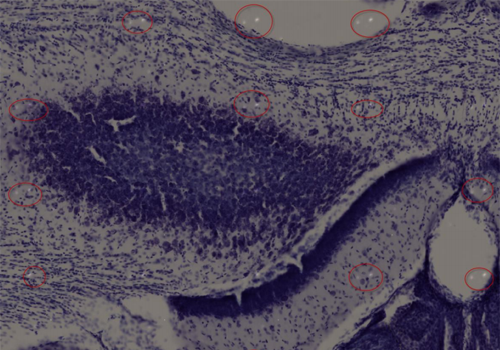

Problem 2: There are bright specks consistently spaced throughout the image which suggest the presence of debris. Solution: